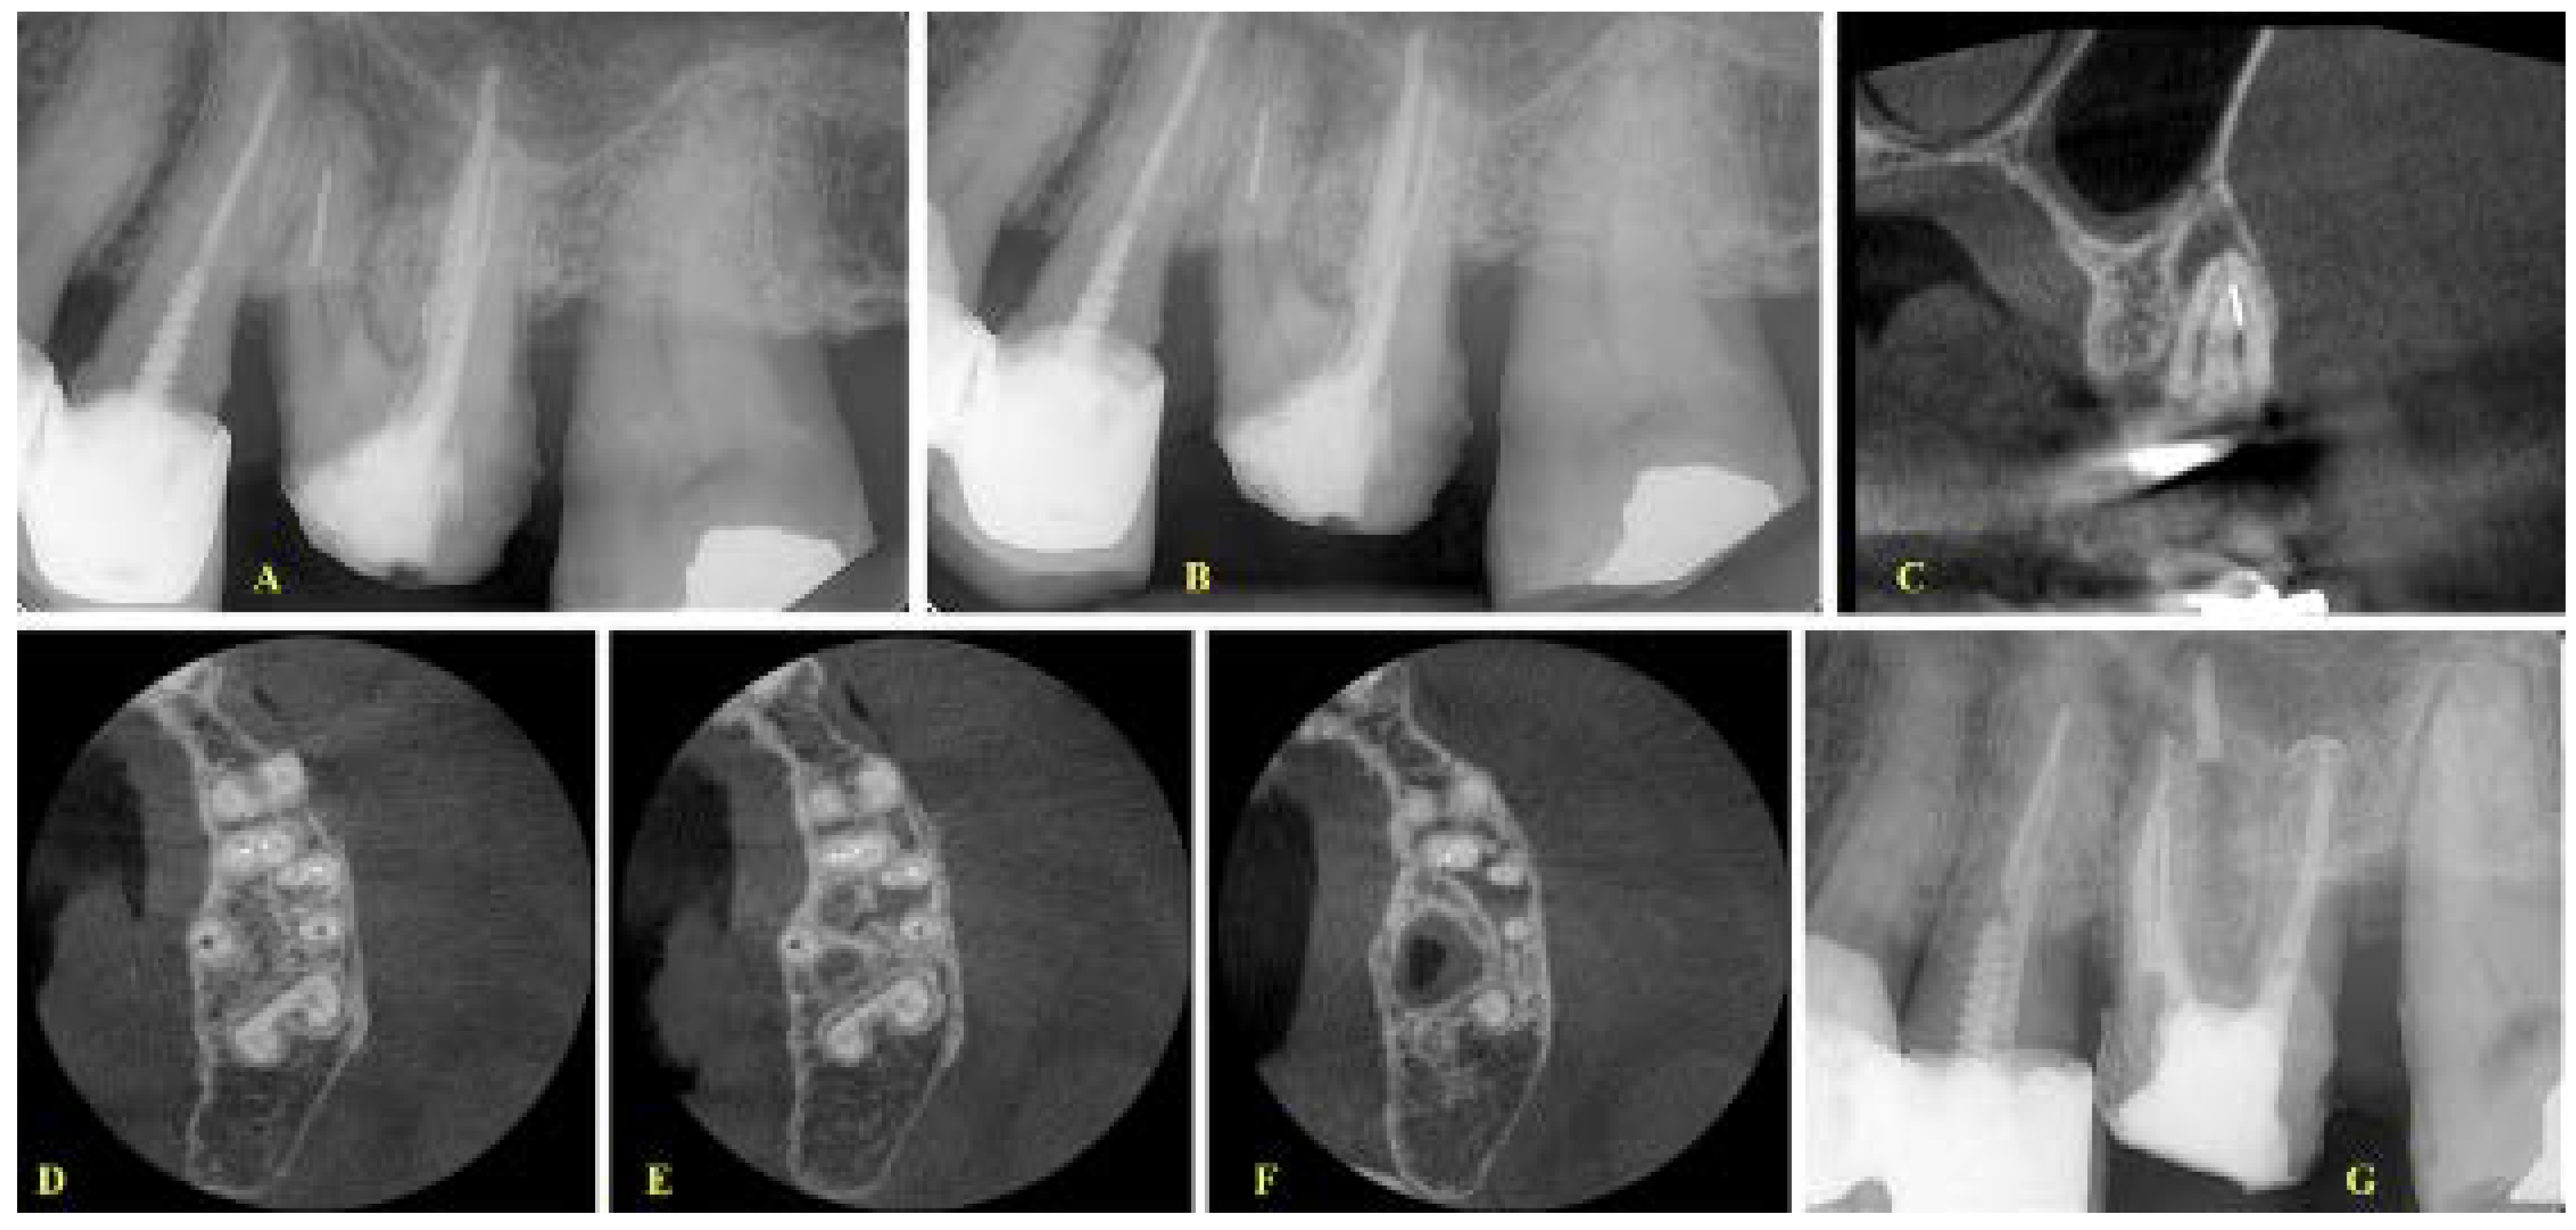

- If the fragment was located at the middle level, the canals were separate and the curvature was not severe as indicated after evaluation of the coronal CBCT images; then, a removal attempt was made, especially in cases where the length of the fragment was short (Figure 2).